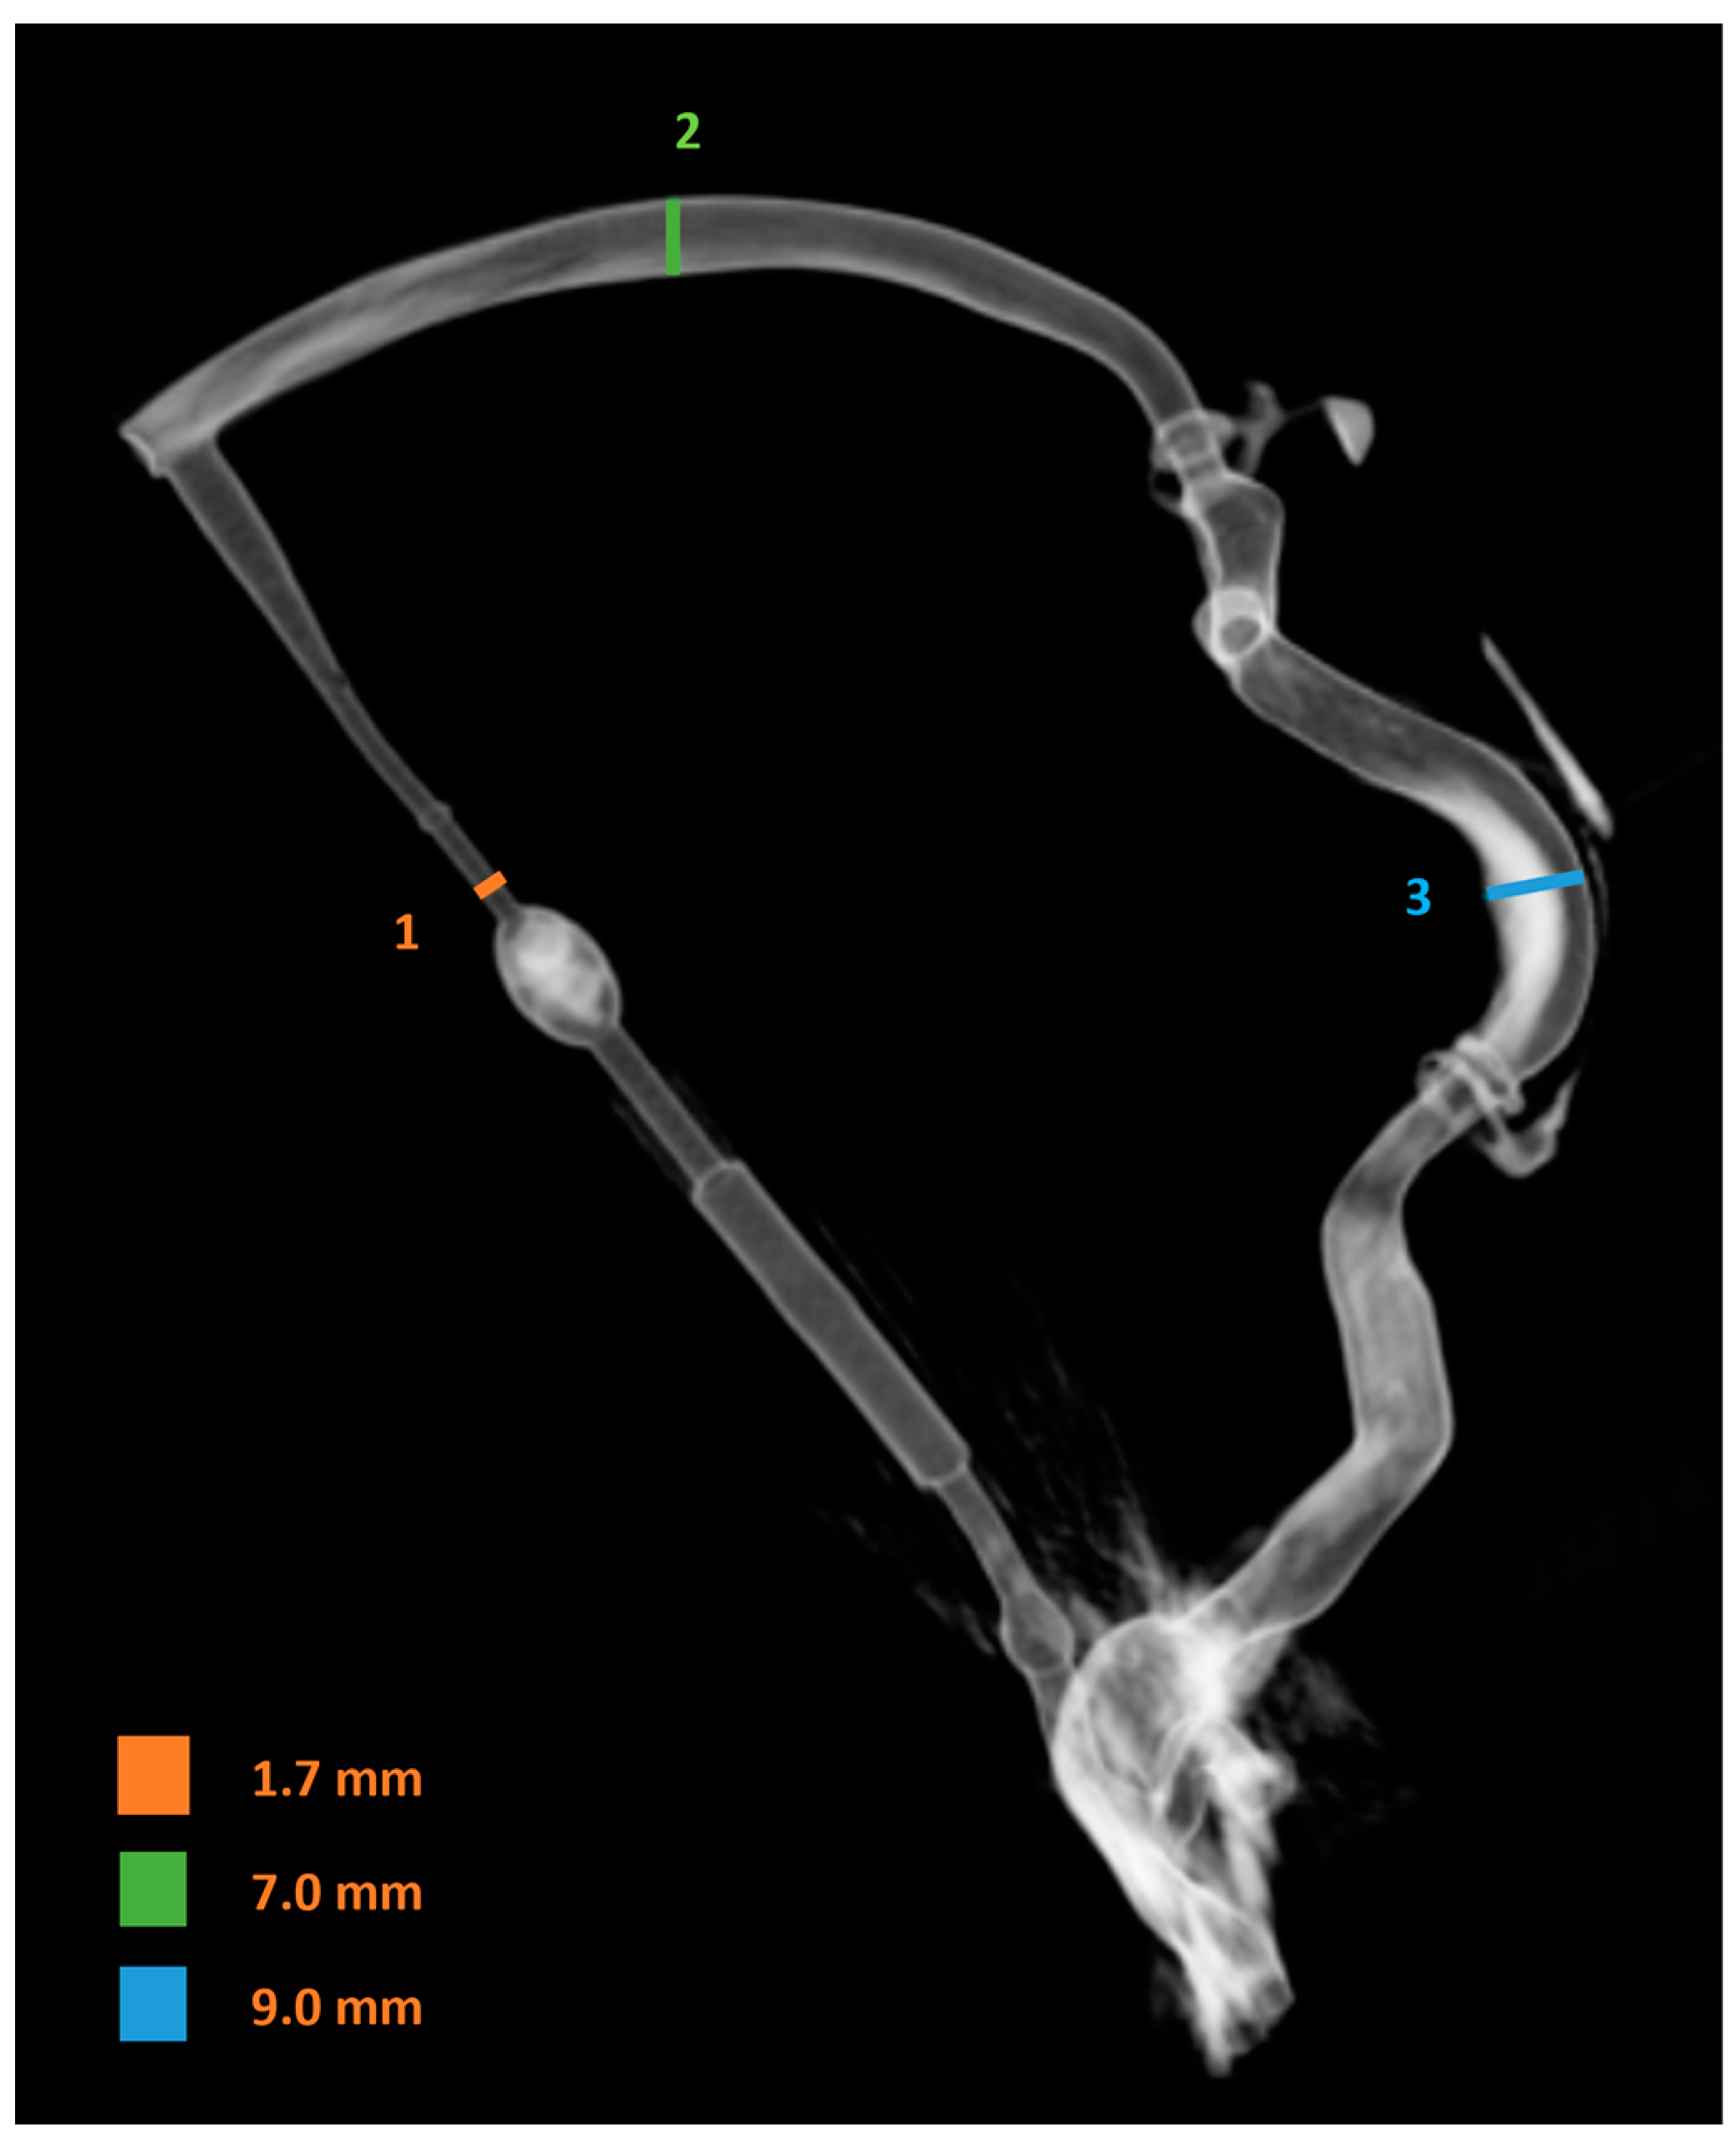

Finally, a 3D DSA image of the venous system was taken, as shown in Figure 6. The image was used to measure the diameter of the vein models. This shows that the vein system behind the throttle had the smallest diameter of 1.7 mm. The superior sagittal sinus had a diameter of 7.0 mm, while the sigmoid sinus had a diameter of 9.0 mm.

Figure 6.

3D DSA image of the venous system for diameter measurement behind the throttle (1), in the superior sagittal sinus (2) and in the sigmoid sinus (3).